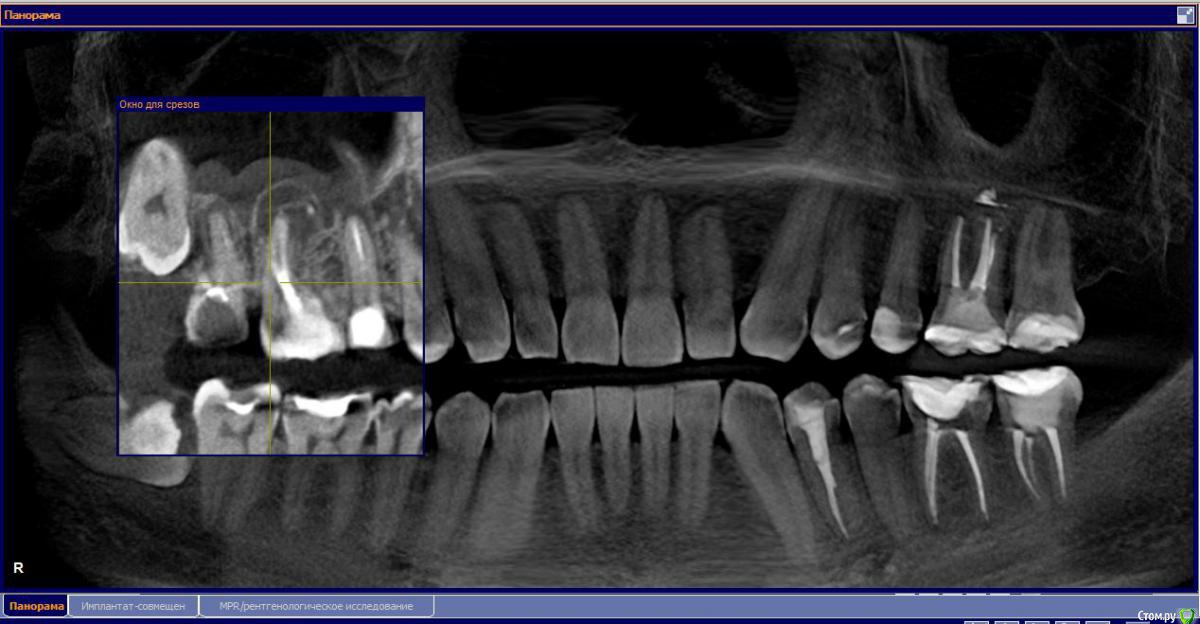

М, 33 года. Есть показания к одновременному удалению 16-го зуба - киста, и 17-го - разрушена верхушка. 8-й предлагают оставить, чтобы "держал кость" (как то так мне озвучили).

Через 3-4 месяца рекомендуют синус-лифтинг и установку двух имплантатов.

- Возможно ли консервативное перелечивание 16 зуба и есть ли смысл?

- Насколько опасная имеется киста?

и 6 и 7й зубы не выглядят 100% кандидатами на удаление.

1.6 большая вероятность сохранить,но понятнее при очном осмотре и диагностическом вскрытии. 1.7,скорее всего,не жилец,но тоже очно взглянуть на него стОит